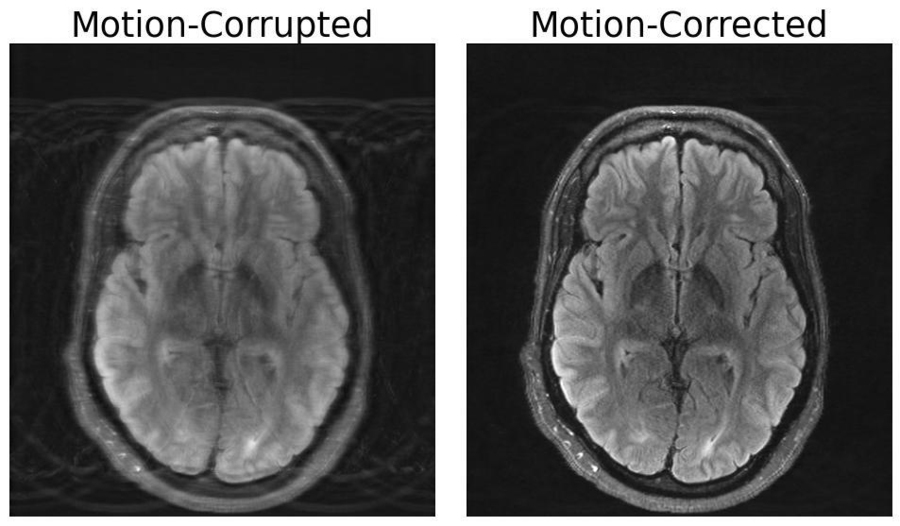

To the untrained eye, a medical image like an MRI or X-ray appears to be a murky collection of black-and-white blobs. It can be a struggle to decipher where one structure (like a tumor) ends and another begins.

When trained to understand the boundaries of biological structures, AI systems can segment (or delineate) regions of interest that doctors and biomedical workers want to monitor for diseases and other abnormalities. Instead of losing precious time tracing anatomy by hand across many images, an artificial assistant could do that for them.